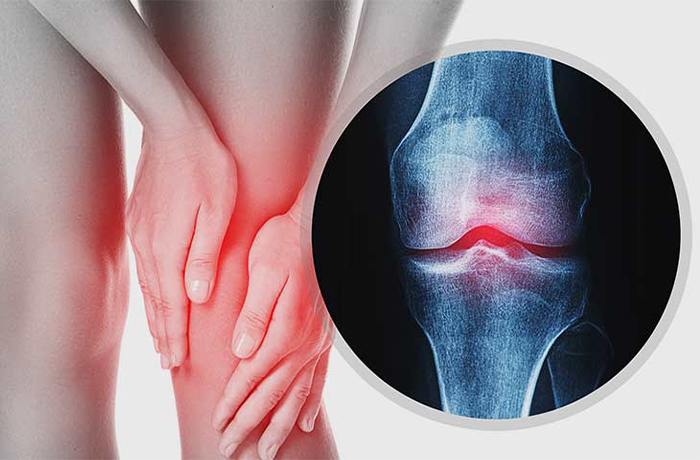

Osteoarthritis is the most common form of arthritis, often considered a degenerative joint disease. But at its core, it's more complex than just cartilage erosion. It involves chronic inflammation, metabolic imbalances, and improper stress on joints — usually the knees, hips, lower back, and fingers. While aging contributes, many patients develop osteoarthritis early due to obesity, injuries, hormonal imbalances, or genetic tendencies. The pain is often persistent and worsens over time, leading to restricted movement and loss of joint function if not addressed early and properly.

Osteoarthritis isn’t a disease that halts on its own. As the cartilage continues to erode, bones may start grinding against each other, leading to swelling, deformities, and eventual immobility. Sadly, many patients only seek treatment when the condition becomes unbearable, by which time surgery may seem like the only option. But it doesn’t have to reach that point. Homeopathy offers a way to intervene earlier — and more holistically — to preserve joint function and slow degeneration.